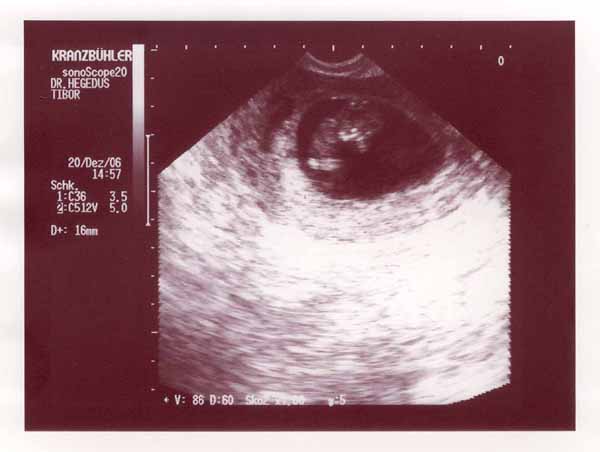

babuci [/img]